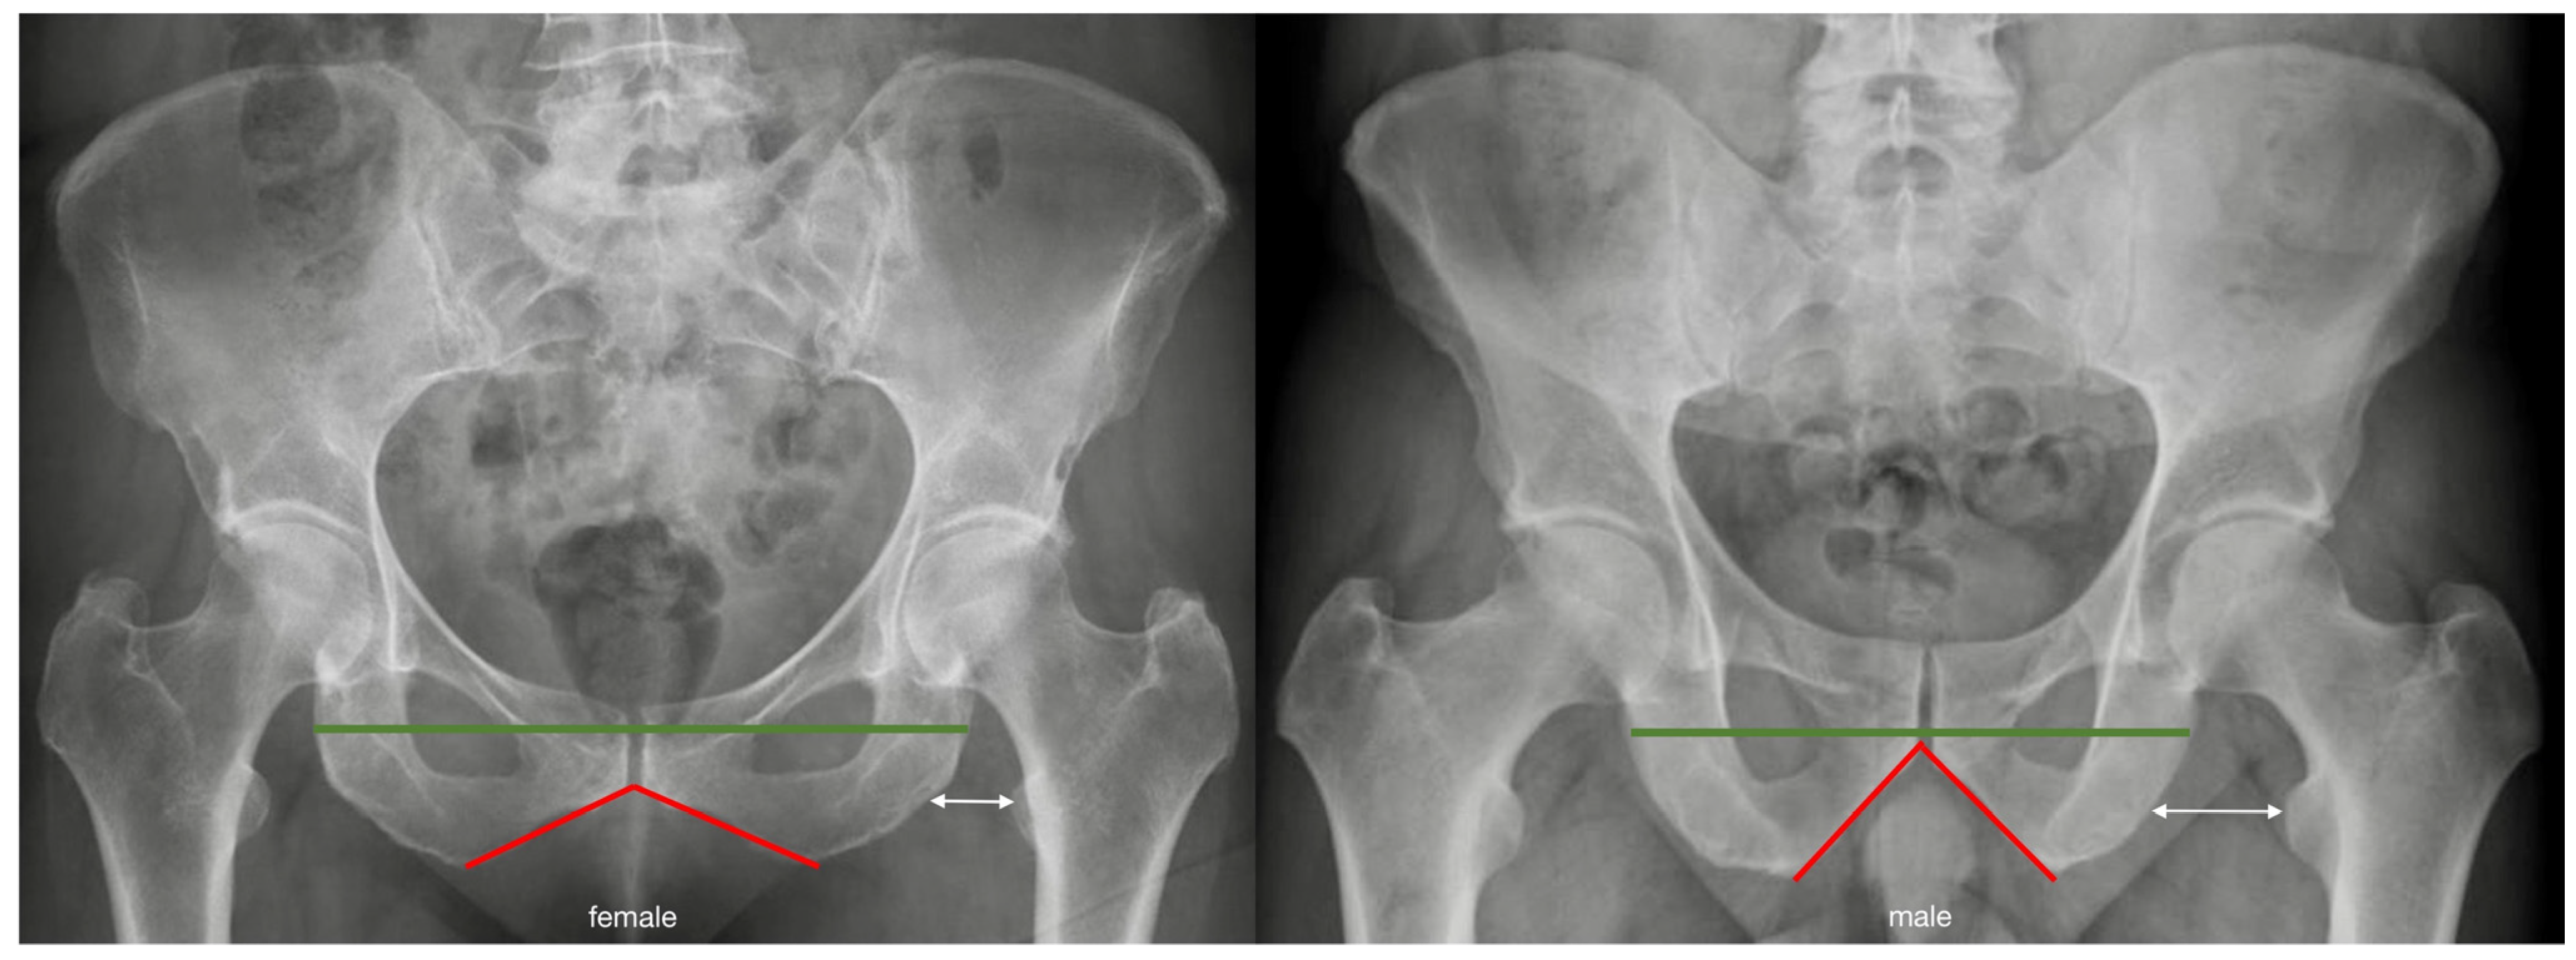

The concepts of ischiofemoral conflicts and posterior hip impingement are gaining more recognition as a mechanistic explanation of hip pain. Interestingly, looking at the published reports of posterior hip impingement, it is obvious that the vast majority of reported cases were female. In a systematic review and meta-analysis by Singer, a total of 154 patients with ischiofemoral impingement were reported by five studies, of whom 133 (86.4%) were female and only 21 were male [14]. Furthermore, the handful of case reports demonstrating representative cases of ischiofemoral impingement have all reported female patients and no males [16,17,18,19,20,21]. The results of this study provide an explanation for this distribution that can clearly be attributed to the pubic-arc angle (also known as the subpubic angle) of the pelvis, which is inherently larger in females due to the obstetric adaptation of the female pelvis [22,23,24]. This ultimately increases the distance between both ischii and shifts the ischii closer to the femur (Figure 8). The ischiofemoral distance is therefore reduced, and the risk of impingement may therefore be increased. This study provides evidence to confirm this phenomenon.

Figure 8. An example of a female pelvis on the left side and a male pelvis on the right. It is obvious that the increased pubic-arc angle (red) and corresponding widening of the interischial distance (green) results in a decrease in the ischiofemoral space (white), putting the female hip at a higher risk of ischiofemoral impingement.